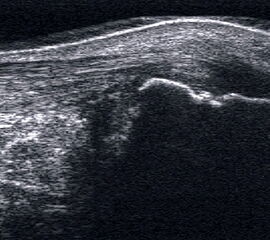

Peronealsehnenluxation

Peronealsehnenluxation. TS an der Fibulaspitze. Die Sehnen sind über die Fibula gerutscht.

Abbildung 45

Lagerung: Rückenlage, Innendrehung des Beins.

Schnittführung: TS und LS hinter dem Außenknöchel.

Referenzstrukturen: Fibulaspitze, Sehnen der Mm. peronaei.

Befunde: Halo-Phänomen. Bei der Luxation rutschen die Sehnen über den Außenknöchel nach lateral/ventral. Eine spontane Reposition unter Entspannung ist möglich. Im TS kann die Instabilität ggf. mittels Provokationstest durch Eversion gegen Widerstand sonographisch dynamisch dargestellt werden. Bei der Diagnostik der Peronealsehnen Instabilität oder Luxation ist die Sonographie durch die Möglichkeit der dynamischen Untersuchung dem MRT klar überlegen 4.